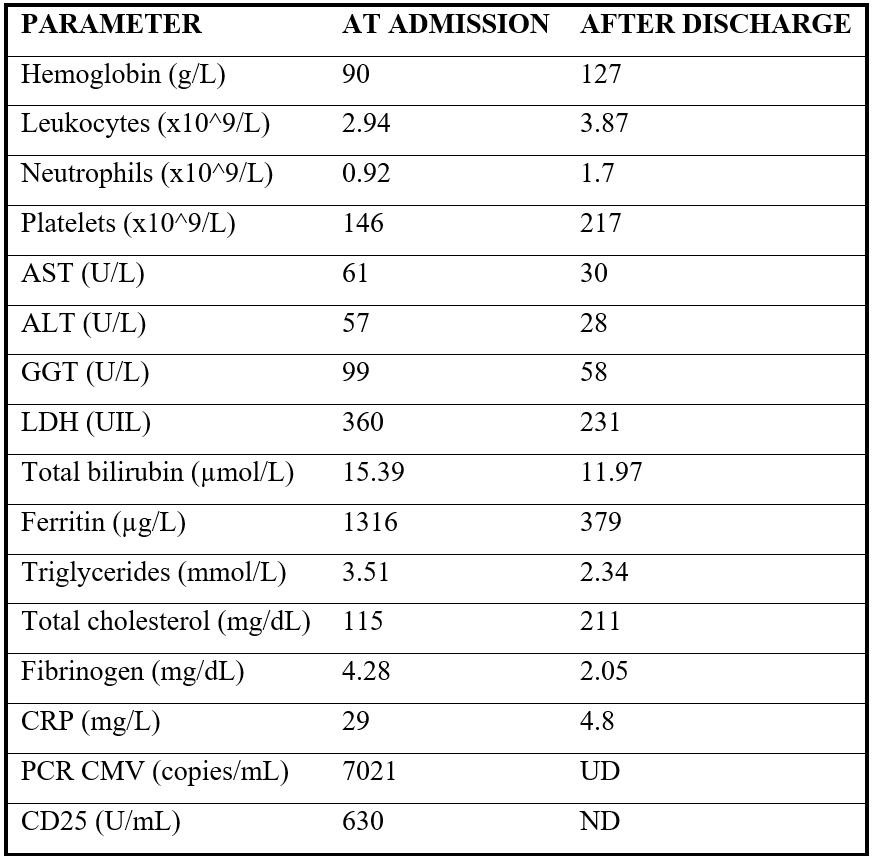

Initial blood tests showed anaemia (haemoglobin of 90 g/L), neutropenia (0.92x109 neutrophils/L), elevated inflammatory markers, hypertriglyceridemia (3,51mmol/L) and high ferritin (1316 µg/L), suggesting a hyperinflammatory state. Liver and renal function were mildly deranged, while coagulation studies, autoimmune panels, hormonal assays and tumour markers were unremarkable (Table 1).

Table 1: Comparative table of our patient´s analytical parameters at admission and after discharge.

ALT: Alanine aminotransferase; AST: Aspartate aminotransferase; CMV: cytomegalovirus; CPR: C-reactive protein; GGT: gamma-glutamyl transferase; PCR: polymerase chain reaction.